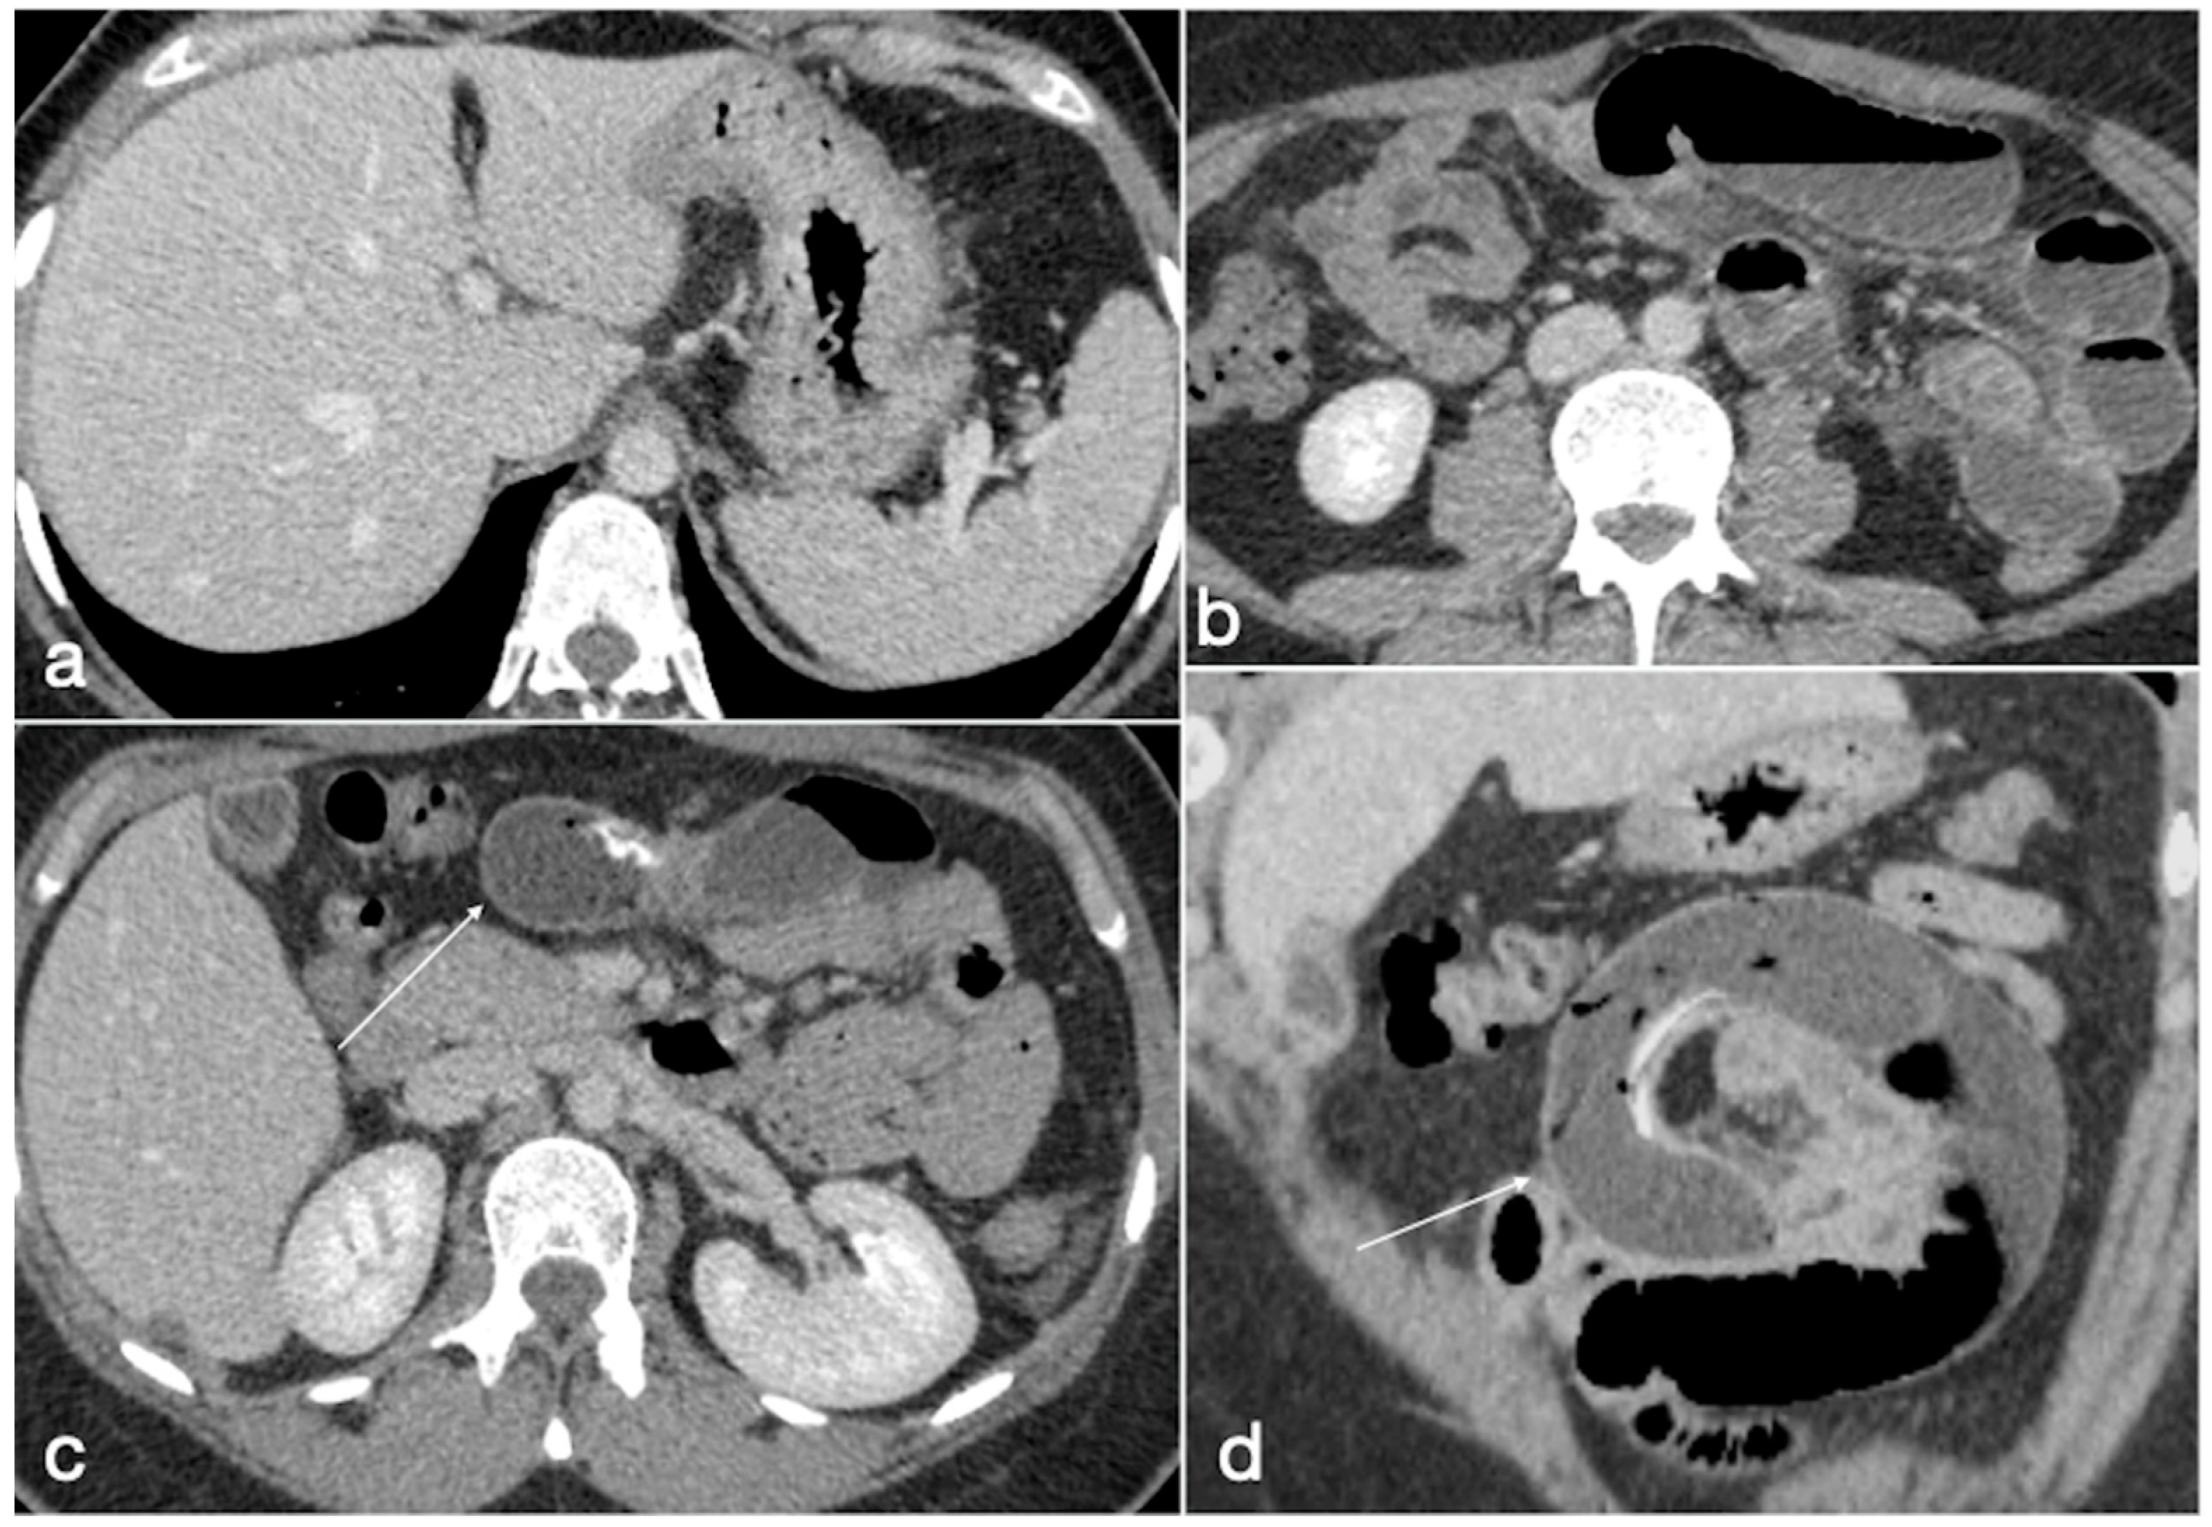

Figure 23. Patient 5. Gastro-bronchial fistula after sleeve gastrectomy. A 52-year-old female was complaining for persistent cough and fever more than one month after sleeve gastrectomy followed by a leak conservatively treated. See the surgical suture of the sleeve gastrectomy (a, axial view, straight arrow), close to which there is a small hyperdensity (a, curved arrow). Furthermore, there is a pulmonary consolidation (b, axial view, circle) in the context of which there is an inhomogeneously hypodense round collection with some air bubbles suspected for pulmonary abscess (b, arrow). This area appears continuously to the gastric suture, and it is best seen in the coronal view (c, arrow). After the hydrosoluble oral contrast administration, this migrates into the abscess (d, axial view; e,f, coronal view; arrows) that was demonstrated to be related to the presence of a gauze.